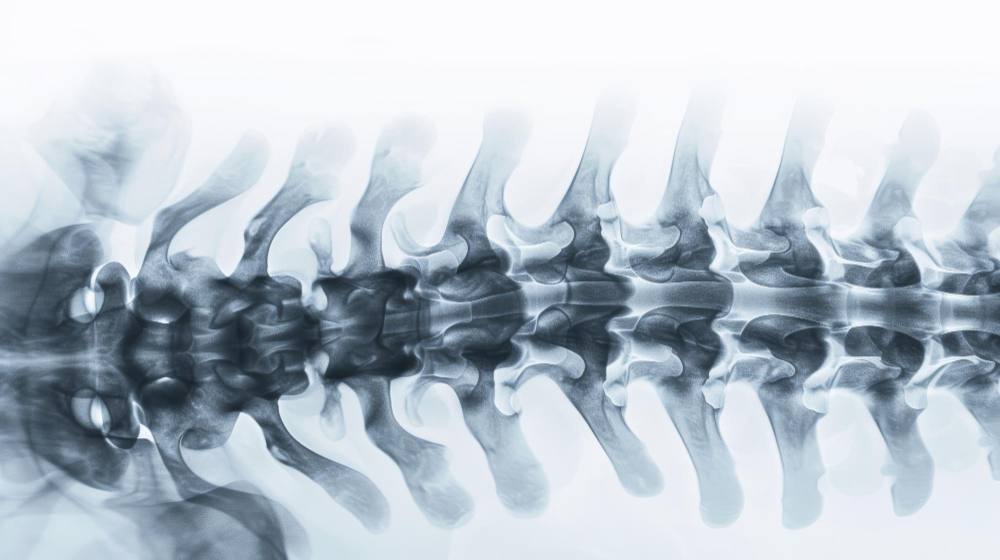

말 그대로 척추 뼈 중 요추 근처의 뼈가 아래 뼈와 연결되는 기능이 상실되어 앞으로 밀려 나오면서 통증을 유발하는 것을 말합니다.

척추 뼈가 앞으로 서서히 미끄러지면서 허리통증과 다리저림 등을 발생

척추 어느 부위에서나 발생 가능하지만 하부 뼈에서 많이 발생

척추(상관절돌기, 하관절돌기)의 기능이 상실되어 상위 척추가 전위되어 생김

문진과 기본적인 상담을 통해 알수 있고 간단한 X-Ray 촬영으로 진단이 가능